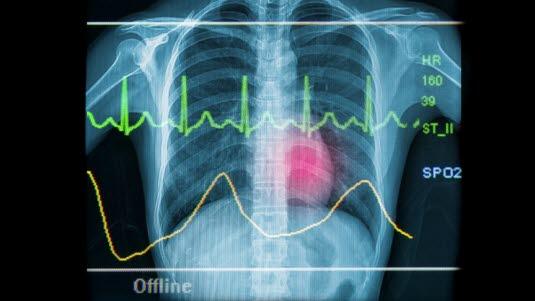

Effektiv blodsirkulasjon krever en rytmisk samordning av forkamrene (atriene) og hjertekamrene (ventriklene) for å få best mulig pumpeeffekt. I tillegg kreves det god kontroll over pulsen, dvs. hastigheten på hjerteslagene. Samordningen av disse to mekanismene utføres via hjertets elektriske system.

Hjerte innvendigHjertet er inndelt i fire kammer med to kammer på høyre og to kammer på venstre side. På hver side er det et forkammer (atrium) og et hjertekammer (ventrikkel) som samarbeider om å pumpe blodet ut i kretsløpet. Kamrene på høyre side pumper blodet ut i lungekretsløpet, og kamrene på venstre side pumper blodet ut i det store kretsløpet via hovedpulsåren (aorta). I forbindelse med et enkelt hjerteslag fungerer de to kamrene på samme side som to pumper. Først trekker de mindre atriene seg sammen og fyller de avslappede ventriklene med blod. Like etter trekker de kraftige ventriklene seg sammen og presser ut blod i kretsløpene samtidig som klaffene til atriene lukkes. Effektiv blodsirkulasjon krever en rytmisk samordning av atriene og ventriklene for å få best mulig pumpeeffekt. I tillegg kreves det god kontroll over pulsen, dvs. hastigheten på hjerteslagene, som normalt er 60-100 slag per minutt når kroppen er i hvile. Samordningen av disse to mekanismene utføres via hjertets elektriske system. Dette systemet fungerer som et tre-trinns system.